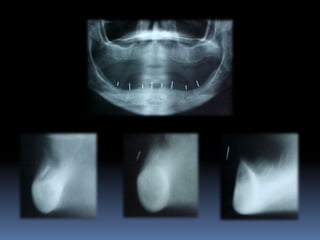

Exames Imaginológicos

Radiografias periapicais, telerradiografias e

panorâmicas;

Tomografias computadorizadas

Softwares de imagens 3D